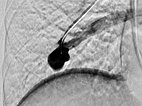

Verschluss der pulmonalen AVM des Oberlappens durch Einbringen von mehreren Platindrahtsprialen (Coils) über den Mikrokatheter unter Schonung der nicht pathologischen Lungenarterien.